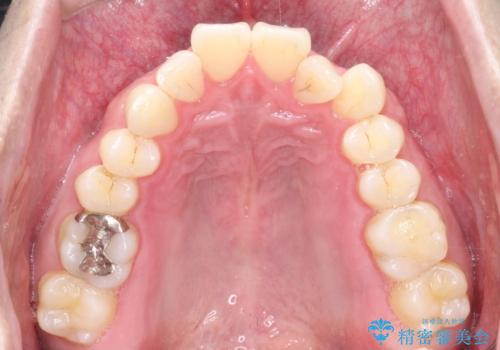

- 前歯の凸凹と顎の偏位を主訴に来院されました。

下顎の偏位を認めましたが、外科矯正を希望されなかったためできる範囲で顎の偏位を治すことができるよう治療を行なっております。

治療開始前に、下顎位の評価をおこなうことで、完成度の高い治療を行うことができました。